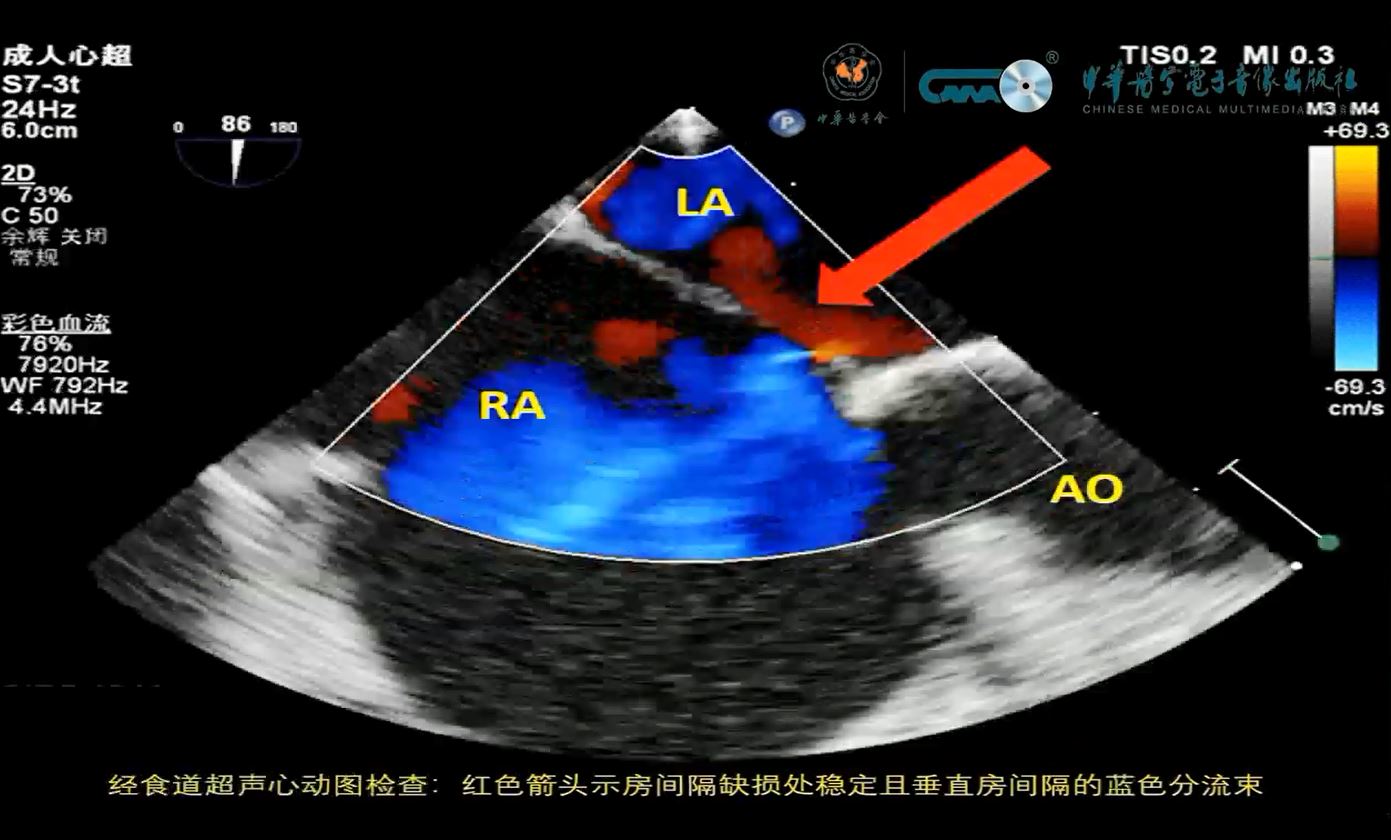

部分型肺静脉异位引流合并房间隔缺损患者术前及术中动态影像资料

孙娅慧, 刘淑萍, 孟利民, 姜礼君, 张红超, 杨斯博, 李利

中华诊断学电子杂志 2025 , 13 (03) : 200 -203 .